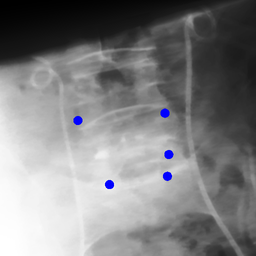

Shift-Invariant Tracking. The POINT network benefits from the shift invariant property of the convolution operation, which makes it less sensitive to the in-plane offset of the DRRs. Figure 8 shows some tracking results from the POINT network. Here the odd rows show the (a) X-ray and (b-d) DRR images. The heatmap below each DRR shows the tracking result between this DRR and the leftmost X-ray image. The red and the blue marks on the X-ray and DRR images denote the POIs. The red and the blue marks on the heatmaps are the ground truth POIs and the tracked POIs, respectively. The green blobs are the heatmap responses and they are used to generate the tracked POIs (blue) according to Equation (7). The numbers under each DRR denote the mPD scores before and after the tracking. As we can observe that the tracking results are consistently good, no matter how much initial offset there is between the DRR and the X-ray image. This shows that our POINT network indeed benefits from the POI convolution layer and provide more consistent outputs regardless of the in-plane offsets.

Refer to caption

(a)

(b) 13.6 \rightarrow 7.3

(c) 22.9 \rightarrow 9.0

(d) 37.1 \rightarrow 7.8

(e)

(f) 19.5 \rightarrow 8.7

(g) 26.0 \rightarrow 9.5

(h) 41.1 \rightarrow 11.4

(b)

(c)

(d)

Figure 8: POI tracking results. (a) X-ray image. (b-d) DRR images with different in-plane offsets. The heatmaps of the tracking results are all aligned with the X-ray images and appear similar, showing the shift-invariant property.